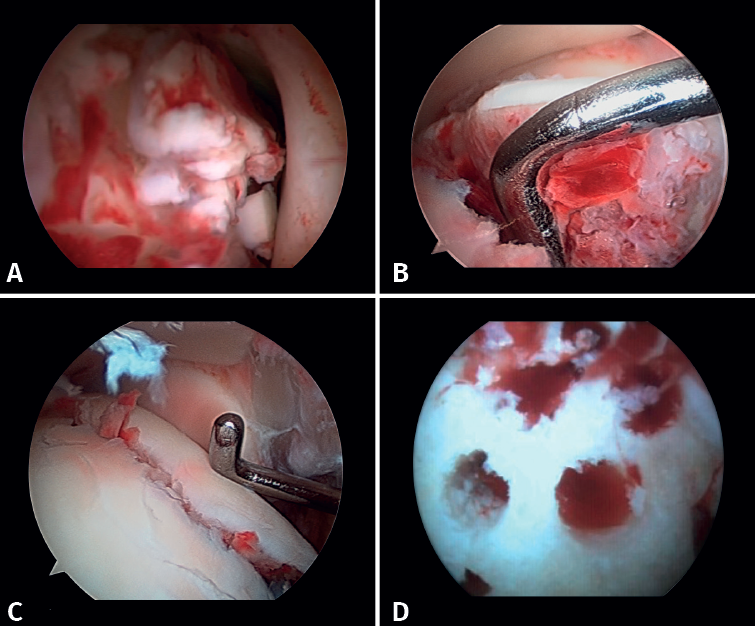

1. Diagnostic and therapeutic arthroscopy

After osteosynthesis of the posterior malleolus, our next step is to perform diagnostic ankle arthroscopy to evaluate concomitant injuries such as OCLs or loose bodies, and to assess reduction of the posterior malleolus, and injuries to the external and internal ligament complex, and the syndesmosis. Although arthroscopy begins after the completion of osteosynthesis of the posterior malleolus, its use extends throughout the surgical procedure. In fractures without involvement of the posterior malleolus, arthroscopy is the first procedure to be performed prior to malleolar synthesis.

- Debridement of the joint and evacuation of the intra-articular hematoma: this could help eliminate proinflammatory markers that may play a role in the prevention of PTOA and reduce the occurrence of arthrofibrosis, which would have a positive effect on the prognosis of the fracture(10).

- Assessment of reduction of the posterior malleolus: arthroscopy can be used to verify reduction of the posterior malleolus(5)(Figure 2).

Lee has described a novel technique using a drill guide with ankle arthroscopy for the reduction of joint fragments in posterior malleolus fractures. In particular, this technique is beneficial for patients with trimalleolar fractures who have a depressed joint fragment, as it allows anatomical reduction and minimizes the need for extensive incisions(11). - Extraction of loose bodies. The presence of loose bodies within the joint is a common finding in ankle fractures. One-third of all arthroscopy patients had intra-articular loose bodies removed during surgery (24 out of 71cases)(12). Arthroscopy allows the precise removal of intra-articular loose bodies, which can cause pain, blockage or limitation of mobility, and damage to the joint cartilage(13).

- Management of chondral injuries. The literature reports the presence of chondral injuries in 34-91% of all ankle fractures. These lesions are frequently located in the talus and are most common in severe fractures, such as Weber C and PER fractures. Patients with cartilage lesions were 3.5 times more likely to develop radiographic osteoarthritis (Kannus arthritis score < 90) and 5 times more likely to have an unfavorable long-term clinical prognosis (American Orthopedic Foot and Ankle Society [AOFAS] score < 90)(14).

If possible, we reinsert unstable osteochondral fragments (Figure 3). In chondral lesions where it is not possible to reinsert the fragment, cartilage repair stimulation techniques can be used(5,13).